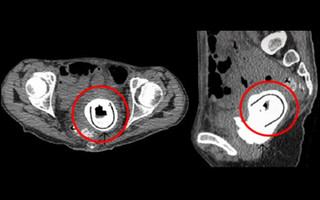

Οι γιατροί έβαλαν τη γυναίκα στο χειρουργείο και τότε ήταν που έπαθαν σοκ! Δεν μπορούσαν να πιστέψουν ότι αυτό που έβλεπαν στους υπερήχους -και εκείνη τη στιγμή ζωντανά- ήταν ένα ερωτικό παιχνίδι μήκους 11 εκατοστών. Τελικά, η γυναίκα παραδέχτηκε ότι το είχε χρησιμοποιήσει με τον σύντροφο της πριν 10 χρόνια και εξήγησε ότι επειδή ήταν μεθυσμένη δε μπορούσε μετά να θυμηθεί αν το είχε αφαιρέσει ή όχι από το σώμα της!

Μετά από ένα μεθύσι ξέχασε να αφαιρέσει το ερωτικό παιχνίδι, που φαίνεται εδώ κυκλωμένο.